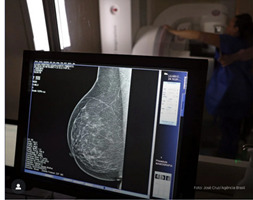

SAÚDE DA MULHER: Lula sanciona lei que amplia mamografia no SUS para mulheres acima de 40 anos

Foto: Agência Brasil

Utilizado para o diagnóstico precoce de câncer de mama, o exame de mamografia gratuito no SUS agora é um direito de toda mulher a partir dos 40 anos. A determinação é da Lei. 15.284, assinada nessa sexta-feira (19), pelo presidente Lula e publicada no Diário Oficial da União.

Antes da nova lei, a recomendação de mamografia pelo SUS era apenas para mulheres entre 50 e 69 anos, faixa que tem mais diagnósticos, segundo o Inca, e a cada dois anos.

O câncer de mama é o que mais mata mulheres no Brasil, segundo pesquisa recente divulgada pelo Instituto Nacional de Câncer (INCA), órgão do Ministério da Saúde.